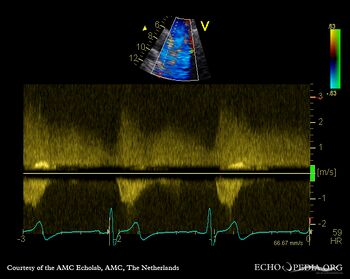

Open ductus Botalli

Courtesy of: AMC Echolab, AMC, The Netherlands

Suprasternal view with Color Doppler Pulsed-wave doppler signal of flow in ductus Botalli